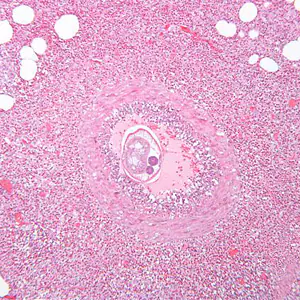

A 47-year-old woman originally from El Salvador had been living in Minnesota for 16 years. She visited family in El Salvador for about a month during the summer. One month after returning to Minnesota, she was admitted to a local hospital for an appendectomy. Biopsy specimens were collected and sent to a pathology lab for routine sectioning and staining. The surgical pathology showed a granulomatous appendicitis with abundant eosinophils with what appeared to be an intravascular helminths. Her absolute eosinophil count was 500. Images (Figures A–D) were captured and sent via email to DPDx for diagnostic assistance. The images in Figures A and C were captured at 100x magnification; the images in Figures B and D at 160x magnification. What is your diagnosis? Based on what criteria?

Figure A